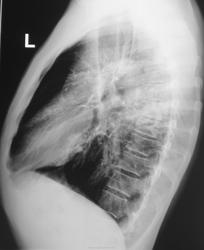

Решили "чиркнуть" боковые томограммы.